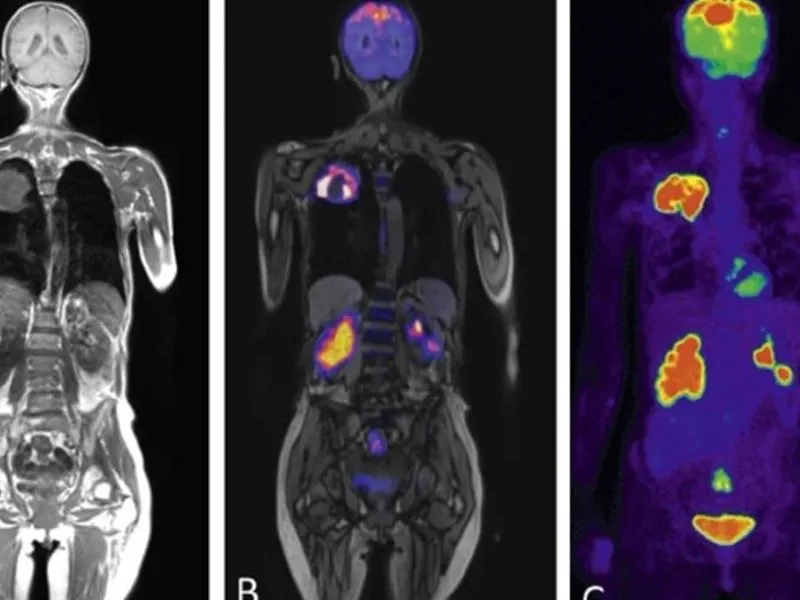

Tüm vücut MR, manyetik rezonans görüntüleme teknolojisi kullanılarak vücudun tamamının ayrıntılı bir şekilde taranmasıdır. Radyasyon içermeyen bu yöntem, manyetik alan ve radyo dalgaları yardımıyla organların ve dokuların yapısını detaylı bir şekilde gösterir. Doktorlar, bu görüntüleri kullanarak hastalıkları teşhis eder ve tedavi planlarını oluşturur.

Tüm vücut MR, genellikle hastalıkların erken teşhisi ve yayılımının değerlendirilmesi amacıyla çekilir. Özellikle kanser taramaları, inflamatuar hastalıklar, enfeksiyonlar ve dejeneratif hastalıkların tespitinde kullanılır. Ayrıca, vücutta mevcut olan anormalliklerin detaylı bir şekilde incelenmesi için de tercih edilir.

Tüm vücut MR ile kanser türleri, tümörlerin yayılımı, inflamatuar hastalıklar, enfeksiyonlar, dejeneratif hastalıklar, sinir sistemi bozuklukları ve damar hastalıkları teşhis edilebilir. Bu yöntem, özellikle erken teşhis gerektiren hastalıklarda büyük önem taşır ve doktorların doğru tedavi yöntemini belirlemelerine yardımcı olur.

Tüm vücut MR ile vücudun iç yapısı detaylı bir şekilde görüntülenir. Kanserler, tümörler, enfeksiyonlar, inflamatuar hastalıklar, sinir sistemi bozuklukları ve damar problemleri gibi birçok hastalık tespit edilebilir. Bu yöntem, hastalıkların erken teşhisi ve tedavi planlaması açısından büyük önem taşır.